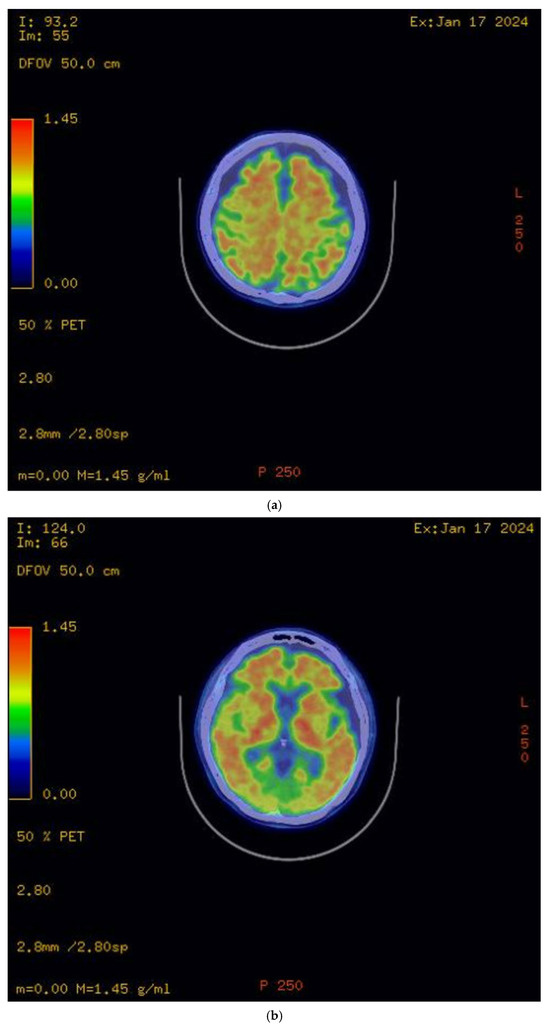

The initial brain MRI conducted in March 2023 demonstrated global cerebral involution with equivocal frontoparietal predilection and relative medical temporal lobe sparing. Global cortical atrophy (GCA) grade 1–2 was reported, showing mild to moderate brain atrophy with a reduced gyri volume, increased sulci and moderate ventricular dilatation [5]. There was evidence of progressive neurodegenerative changes in the brain MRI findings one year later; the second brain MRI in April 2024 showed predominant bilateral frontal and parietal volume loss, sparing the occipital and temporal lobes. A medial temporal lobe atrophy score (MTA) of grade 1 was reported (Figure 2). Amyloid positron emission tomography (PET) (Figure 3) confirmed the presence of amyloids, a hallmark of Alzheimer’s disease. While a lumbar puncture to measure cerebrospinal fluid (CSF) biomarkers (Aβ1-42 and tau) was offered, the family declined due to the invasive nature of the procedure.

Figure 3.

Amyloid PET scan. (a) Radiotracer uptake detected in bilateral frontal and parietal lobes; (b) radiotracer uptake detected in bilateral temporal lobes.

The diagnosis of Alzheimer’s disease (AD) in this case was based on the revised criteria for the diagnosis and staging of Alzheimer’s disease: Alzheimer’s Association Workgroup [6]. AD is defined by its biology, and therefore, a biomarker that can accurately detect AD neuropathologic changes (ADNPCs) or a validated surrogate is sufficient to establish the diagnosis of this disease. Diagnosing AD via abnormal amyloid PET (or biofluid Core 1 biomarkers validated against amyloid PET) in symptomatic individuals in this case is sufficient and meets the criteria based on the recommendations by the Alzheimer’s Association Workgroup. Amyloid PET scans and CSF AD biomarkers are core biomarkers commonly used for AD diagnosis. While both are valuable, amyloid PET scans are less invasive than CSF biomarker testing, making them a more acceptable option for some patients. Blood-based biomarker testing is another less invasive alternative, and advancements in technology have led to some blood-based biomarkers achieving a sensitivity and specificity comparable to CSF-based biomarkers. However, due to the limited availability of blood-based biomarker testing at our facility, these diagnostics are currently inaccessible onsite. Furthermore, sending samples to overseas laboratories would result in significant delays and substantial costs—a significant concern for the patient and her family.